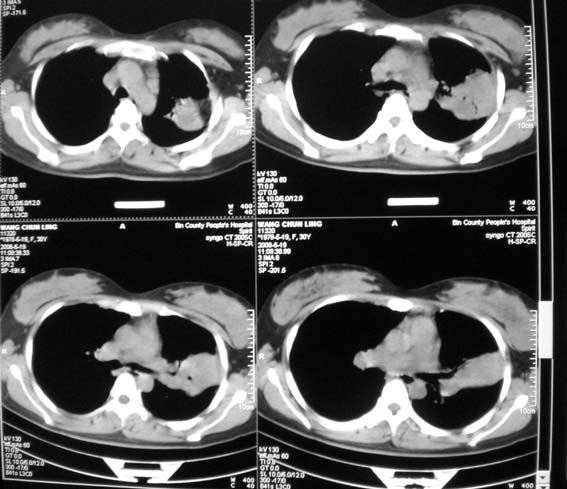

标题: CT13529:肺结核?请会诊!

女,30岁,怀孕后3个月,拍片时肺结核,抗结核治疗4个月复查。

前段支气管通畅,但尖后段支气管闭塞,建议支纤镜除外肺癌,有原片吗,对比一下了。

结核.前段支气管通畅,但尖后段支气管闭塞,建议支纤镜除外肺癌

纵隔淋巴结肿大,见意出外占位